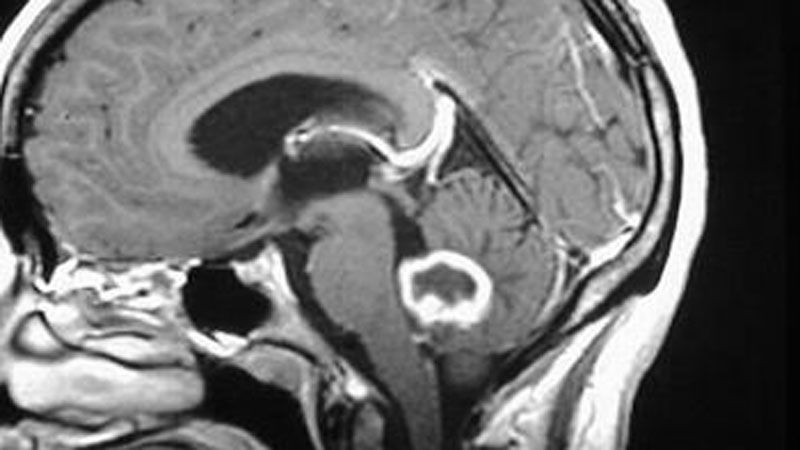

Diseñan fármaco capaz de detener el crecimiento del cáncer cerebral más común

Se trata de uno tipo de cáncer que es muy difícil de extirpar.

El glioblastoma multiforme es uno de los tumores más prevalentes y mortales del cerebro. No en vano, se trata de un tipo de cáncer muy difícil de extirpar quirúrgicamente y altamente resistente tanto a la quimioterapia como a la radioterapia, lo que provoca que la supervivencia media de los pacientes no supere, aún en la actualidad, los 15 meses. Pero, ¿por qué este tumor es tan difícil de tratar? Pues, básicamente, porque aún no se ha encontrado la manera de erradicar todas las células madre del glioblastoma, esto es, las células responsables tanto del crecimiento como de la recurrencia tumoral. Y con que solo quede una de estas células, proliferará y el cáncer volverá a aparecer. De ahí la importancia de un estudio dirigido por investigadores de la Universidad de Alabama en Birmingham (EE.UU.), en el que no solo se describe el mecanismo molecular que utilizan las células madre del glioblastoma para sobrevivir y llevar a cabo su labor cancerígena, sino que se muestra un fármaco capaz de echarlo por tierra.